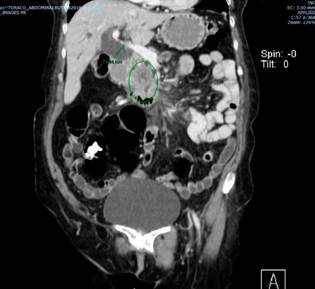

This is the case of a 72-year-old female patient with a biliary obstruction secondary to a mass located in the head of the pancreas. The following findings were reported in her paraclinical tests: laboratory tests: initial total bilirubin levels of 12.32 mg/dL at the expense of direct bilirubin levels (10.8 mg/dL); abdominal CT scan: presence of a neoplasm in the head of the pancreas surrounding in 180° the superior mesenteric vein; patent splenoportal confluence; patent hepatic artery; dilatation of the intrahepatic and extrahepatic biliary ducts, and of the main pancreatic duct; increased density of mesenteric fat with lymph nodes with short axes (between 5 mm and 6 mm) suspicious due to their enhancement; and focal hepatic lesion in the segment 6 with an appearance suggestive of suspected neoplastic infiltration, without presence of free fluid (Figures 1 and 2).